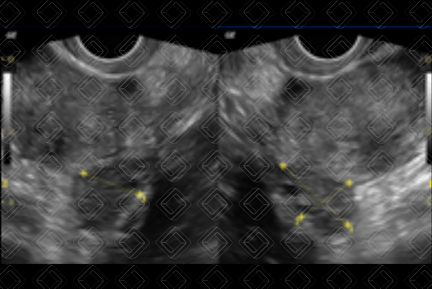

Descrição das figuras 3 e 4: Paciente do sexo feminino, 19 anos. Ultrassonografia da pelve feminina, estudo suprapúbico, evidenciando formação ovalada, anecoica, medindo 3,0 cm, no ovário esquerdo, devendo representar cisto funcional (seta vermelha).

Cistos simples (figuras 1, 2, 3 e 4): Se apresentam na ultrassonografia pélvica como lesões anecoicas, com reforço acústico posterior, unilocular, sem septos ou componentes sólidos no seu interior e não vascularizadas. A maioria dessas lesões é de cistos funcionais e ocorre na pré-menopausa. No entanto, vale a pena lembrar que, apesar de raras, essas lesões também podem ocorrer na pós-menopausa. Diante de uma lesão ovariana cística simples, o acompanhamento é sugerido baseado nas suas dimensões.